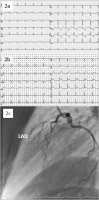

Abbildung 1a-c: 1. (a): Initial ECG showing anterior STEMI; (b): First coronary angiography showing no obstruction/stenosis of the left descending coronary artery (LAD). Right coronary artery and circumflex artery also showed no abnormalities; (c): Global left ventricular function was reduced moderately with anterolateral, apical as well as inferior hypokinesis.